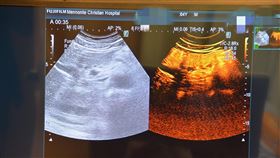

「對比劑超音波」小腫瘤也能抓 存活率↑

65歲陳先生是B肝帶原者,年初經腹部超音波檢查發現肝...